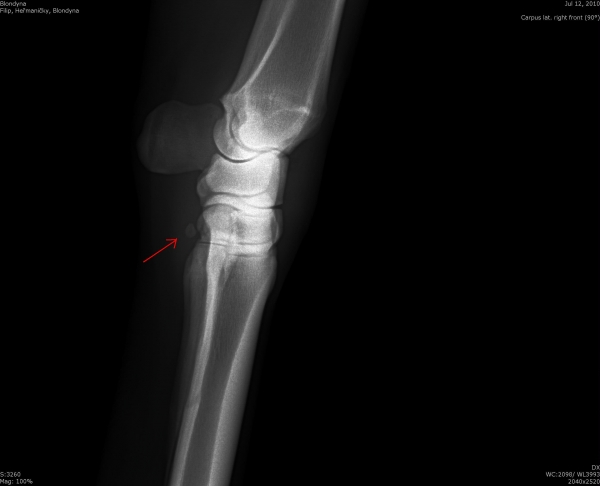

Fragment na spěnkové kosti

rentgenologické vyšetření